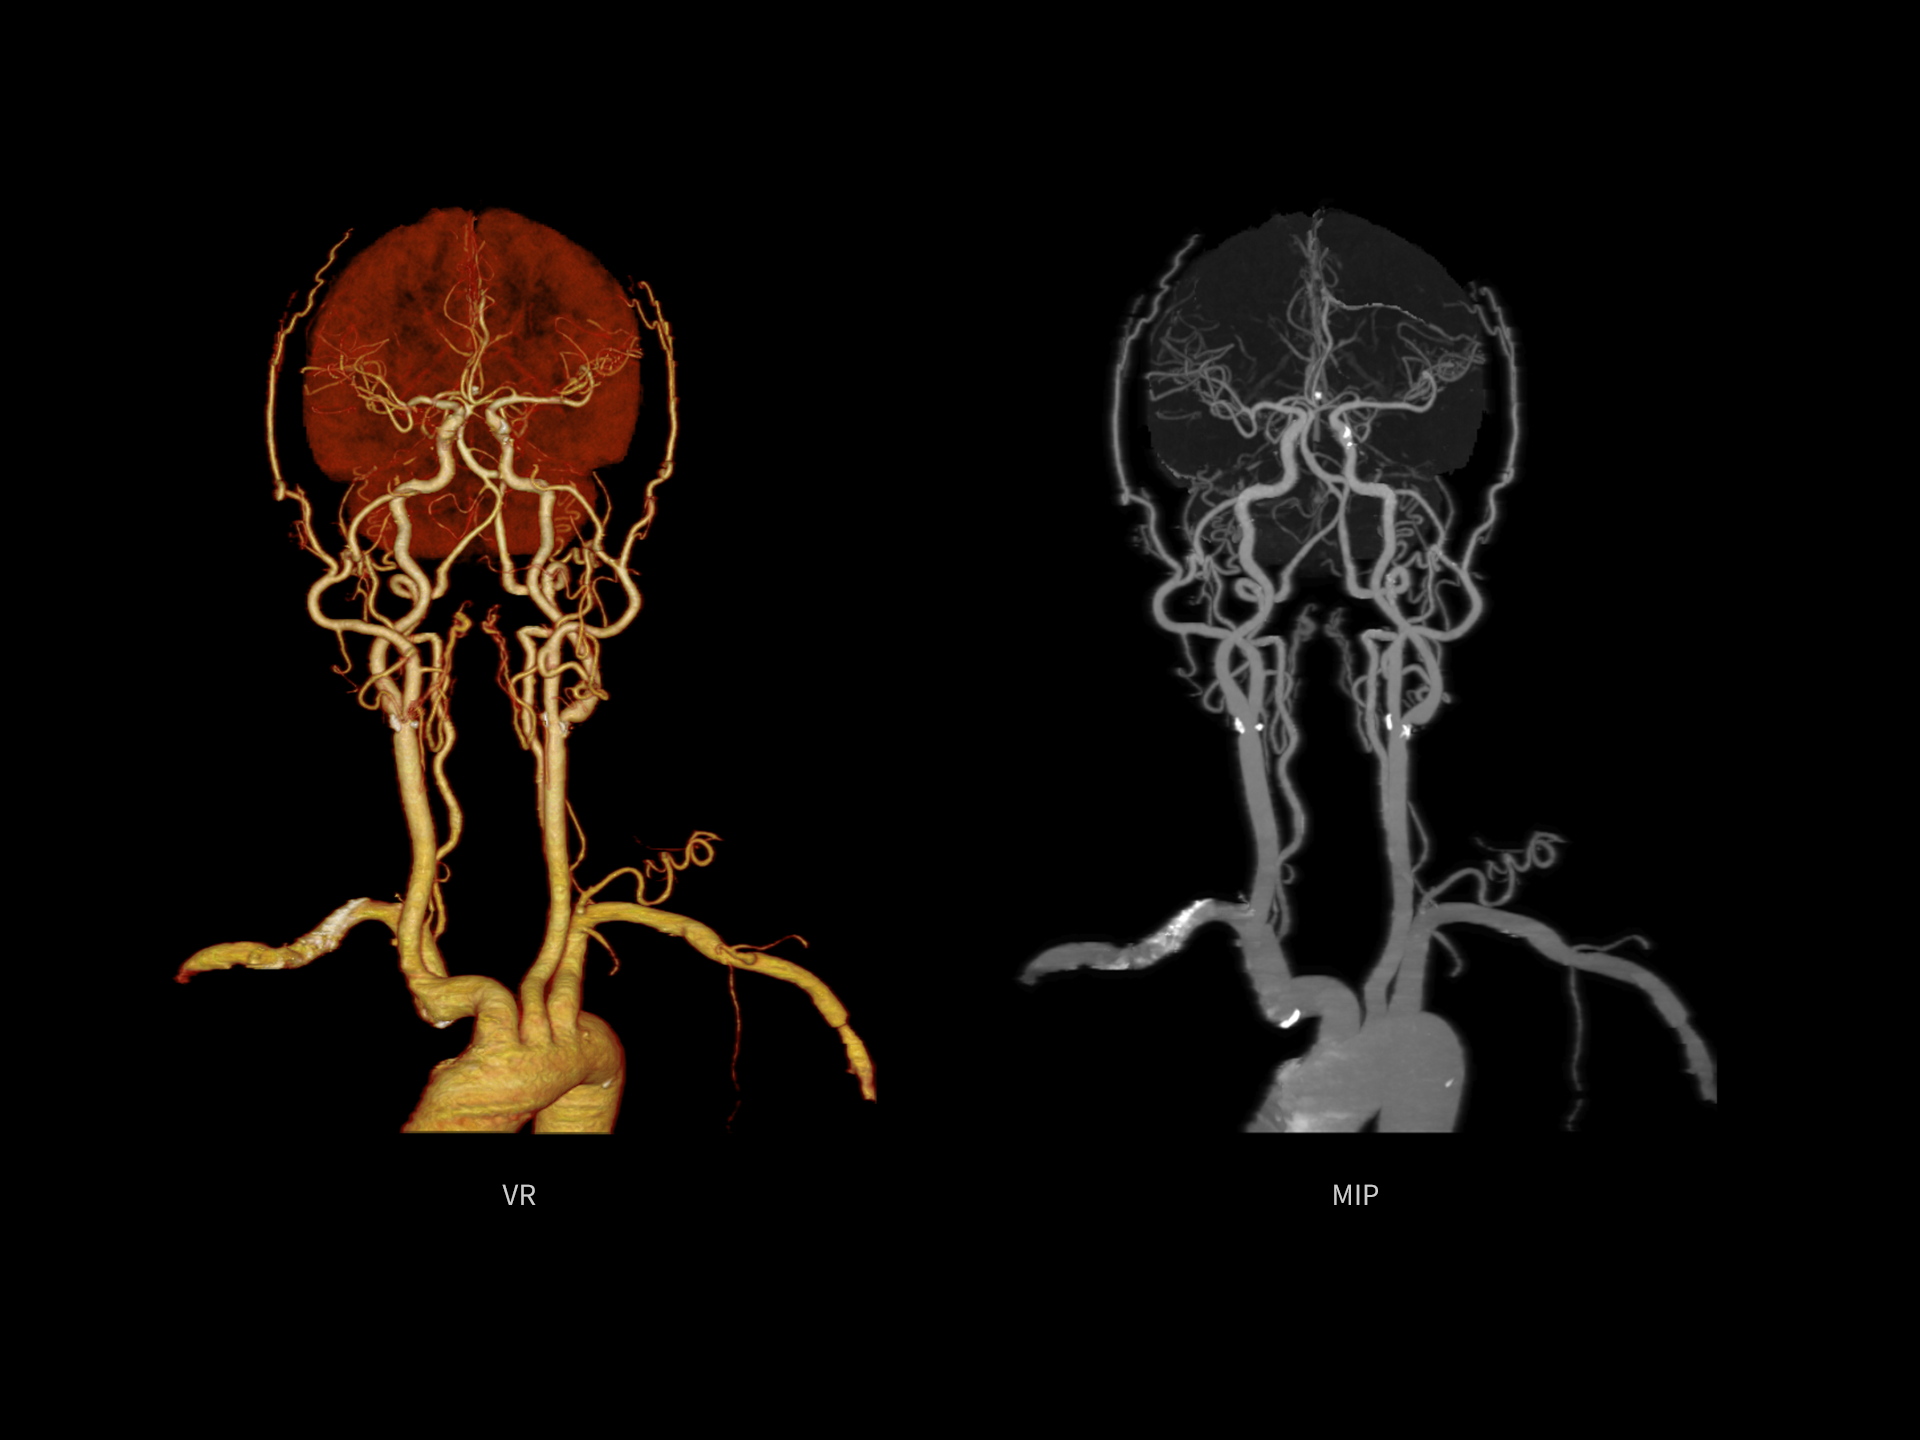

Imagini CTA pentru membrele inferioare